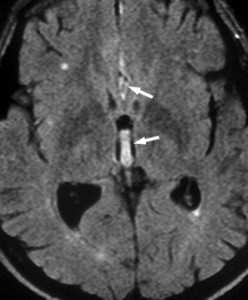

МРТ головного мозга. Аксиальная МРТ типа FLAIR. Аневризма и САК, внутрижелудочковое кровоизлияние.

Субарахноидальное кровоизлияние опасно вазоспазмом, который наблюдается на 5-7 сутки. Сам спазм хорошо определяется при дуплексном сканировании. При МРТ головного мозга можно выявить ранние признаки ишемического инсульта.

МРТ головного мозга. Диффузионно-взвешенная МРТ последовательность. ОНМК в острой стадии вследствие вазоспазма.